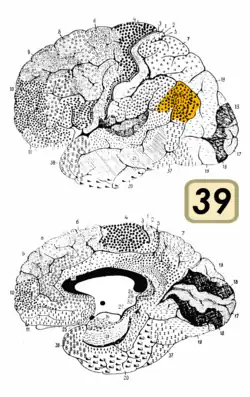

Brodmann area 39, or BA39, is part of the parietal cortex in the human brain. BA39 encompasses the angular gyrus, lying near to the junction of temporal, occipital and parietal lobes.

This area is also known as angular area 39 (H). It corresponds to the angular gyrus surrounding the caudal tip of the superior temporal sulcus. It is bounded dorsally approximately by the intraparietal sulcus. In terms of its cytoarchitecture, it is bounded rostrally by the supramarginal area 40 (H), dorsally and caudally by the peristriate area 19, and ventrally by the occipitotemporal area 37 (H) (Brodmann-1909).